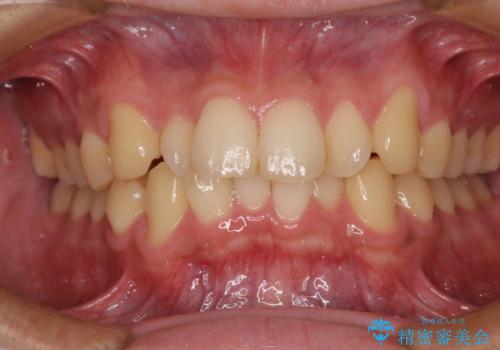

前歯と奥歯のガタガタを矯正で改善

担当医 河口智英